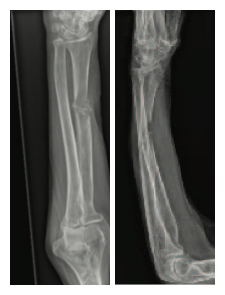

Diagnosis: Metastatic Renal Cell Carcinoma with pathologic fracture of the right radius and left ulna and significantly compromized bone quality.

Description of fracture: Pathologic fracture at the radial shaft with bony destruction measuring 5.8 cm; pathologic fracture mid-ulna measuring

5.2 cm with soft tissue component

Right Radius

Pre-op